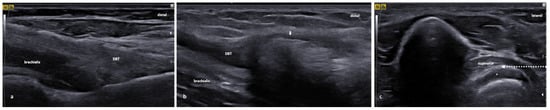

3.3. Distal Biceps Tendinopathy

3.3.1. Essential Anatomy

3.3.2. US Scanning and Guided Injection